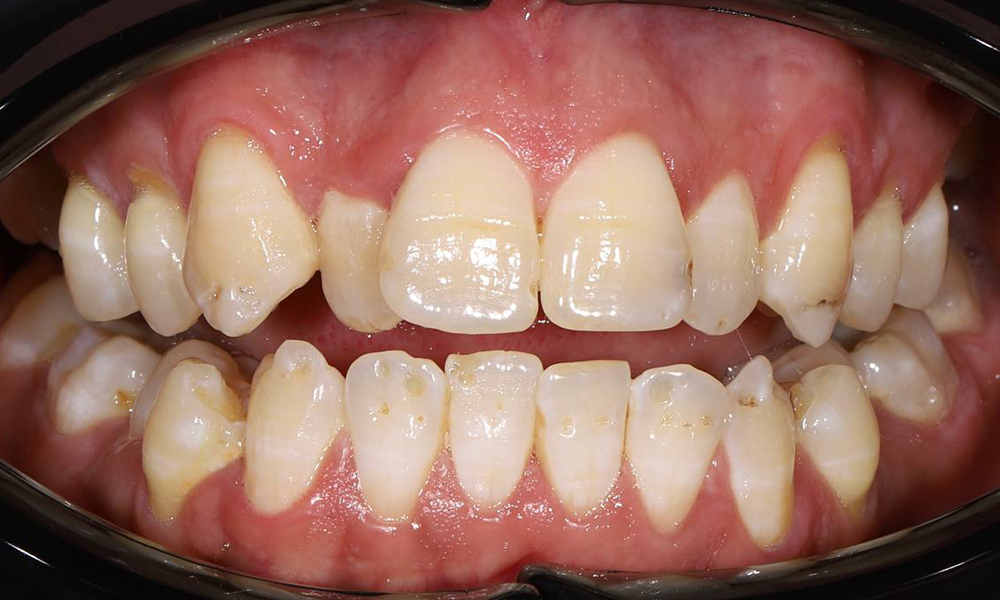

Комплексное ортодонтическое лечение у девушки с множественными нарушениями прикуса на фоне врождённой адентии боковых резцов